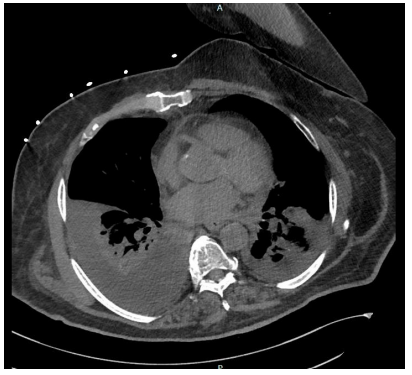

Investigation revealed a white blood cell count (WBC) of 6.0 x 10 /mm3, hemoglobin of 12.9 g/dL, and creatinine of 3.25 mg/dL (baseline of 1.4-1.9). Liver function and lactate were within normal limits. Chest X-ray demonstrated severe rightsided pleural effusion with complete opacification of right hemithorax (figure 1), prompting further evaluation. A chest CT scan performed on 5/12/2023 (2nd day of admission), showed a large right and small left pleural effusion with lower lobe atelectasis and mild ground-glass opacities in right upper lobe without any associated adenopathy (figure 2).